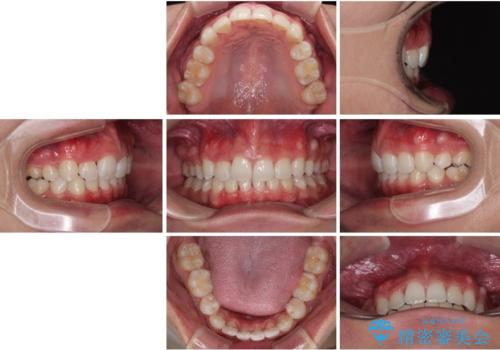

- 「前歯のデコボコが気になる」「前歯の中心がずれていて気になる」とご相談に来られた患者様の症例です。

診察の結果、上下の歯が並ぶためのスペースが不足しており、特に上顎右側の側切歯が内側(口蓋側)に転移していたため、正中が大きく右にずれている状態でした。

上下左右の第一小臼歯を抜歯してスペースを確保する計画を立てました。

矯正装置には白いプラスチックブラケットと白いコーティングワイヤーを使用し、見た目にも配慮した治療を行いました。

治療後には、デコボコと正中の位置が改善し、見た目だけでなく歯磨きがしやすい清潔なお口の環境を手に入れました。